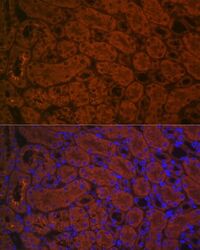

- Submitted by

- Invitrogen Antibodies (provider)

- Main image

- Experimental details

- Immunohistochemistry (Immunofluorescence) analysis of ACE2 in mouse kidney. Samples were incubated with ACE2 Polyclonal antibody (Product # PA5-88732) using a dilution of 1:100 (40x lens). Blue: DAPI for nuclear staining.